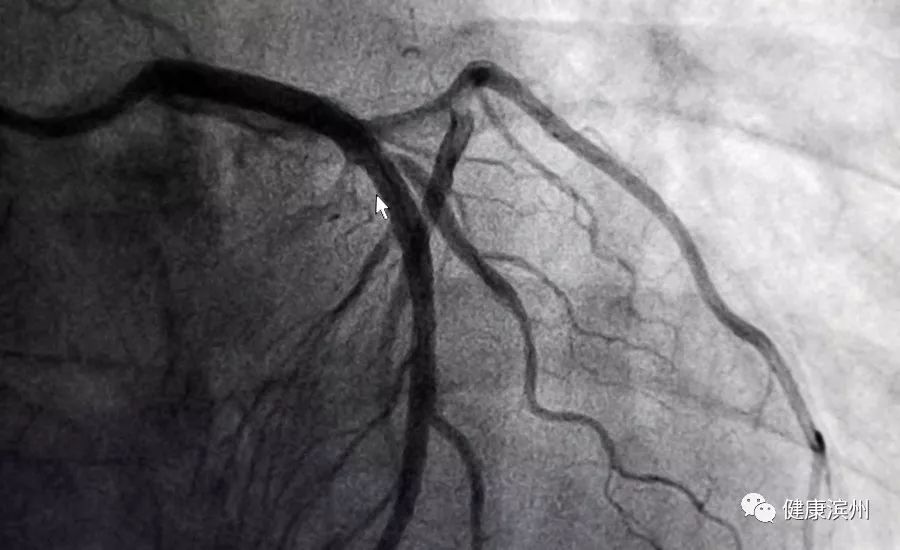

術后,病灶消失的無影無蹤,血管像航拍大地的河流,恢復了奔流不息的景象。